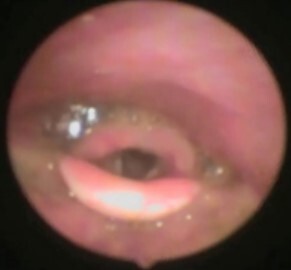

嚥下内視鏡検査

細いファイバーのカメラ(内視鏡)を使って、飲み込みが起きる「ノドの奥」を直接観察します。鼻から内視鏡を入れる違和感はありますが、ノドの状態や日ごろ食べている食事のまま確認できるという利点があります。

細いカメラでノドの奥を直接観察します。